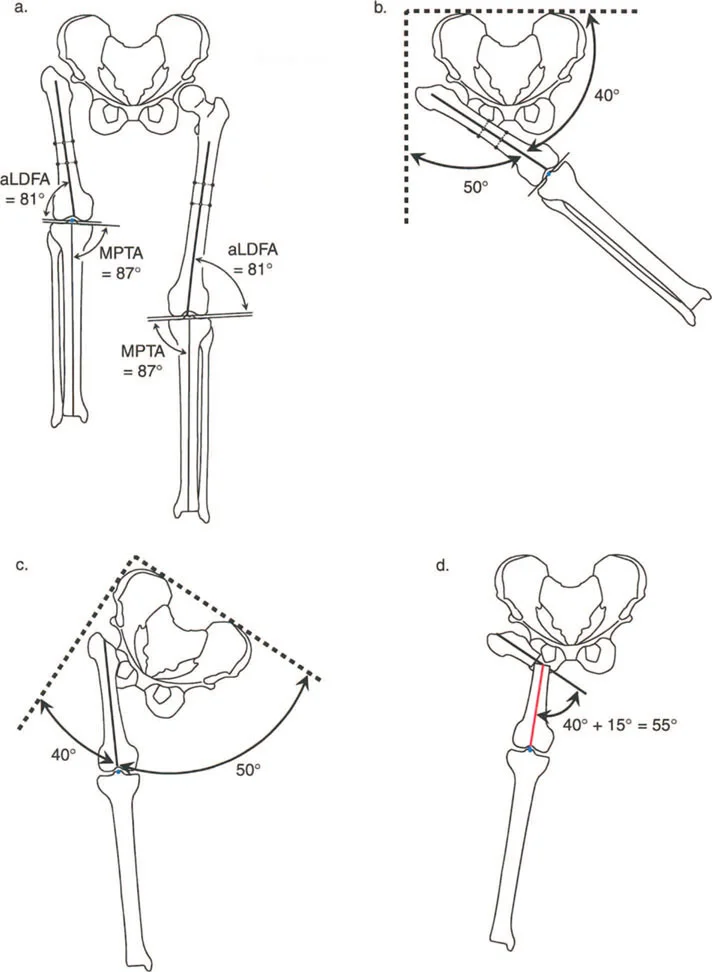

المحور الميكانيكي وانحرافه

تخيل خطًا مستقيمًا يمتد من مركز مفصل الورك إلى مركز مفصل الكاحل. هذا الخط يمثل "المحور الميكانيكي" للطرف السفلي. في الساق الطبيعية والمستقيمة، يمر هذا الخط تمامًا عبر مركز مفصل الركبة. عندما ينحرف هذا الخط إلى الجانب الإنسي (الداخلي) أو الوحشي (الخارجي) لمركز الركبة، فإننا نطلق على هذا الانحراف "انحراف المحور الميكانيكي (MAD)". كلما زاد هذا الانحراف، زاد الضغط غير المتوازن على مفصل الركبة، مما يؤدي إلى تآكل الغضاريف بمرور الوقت.

زوايا اتجاه المفاصل

إن استعادة المحور الميكانيكي إلى وضعه الطبيعي هو جزء من المعركة فقط. فالساق المستقيمة التي تحتوي على مفاصل "معوجة" ستتدهور بسرعة. تقيس زوايا اتجاه المفاصل العلاقة بين المحور الميكانيكي (أو التشريحي) للعظم وخط المفصل الخاص به. هذه الزوايا ضرورية لضمان توزيع الحمل بالتساوي عبر سطح المفصل:

- الزاوية الفخذية الأنسية البعيدة (mLDFA): تقيس اتجاه مفصل الركبة بالنسبة لعظم الفخذ. يتراوح المعدل الطبيعي عادةً بين 85 درجة و 90 درجة (بمتوسط 88 درجة).

- الزاوية الظنبوبية القريبة الأنسية (MPTA): تقيس اتجاه مفصل الركبة بالنسبة لعظم الساق (الظنبوب). يتراوح المعدل الطبيعي عادةً بين 85 درجة و 90 درجة (بمتوسط 87 درجة).

- الزاوية الظنبوبية البعيدة الوحشية (LDTA): تقيس اتجاه مفصل الكاحل بالنسبة لعظم الساق (الظنبوب). يتراوح المعدل الطبيعي عادةً بين 86 درجة و 92 درجة (بمتوسط 89 أو 90 درجة).

منهجية مركز دوران الزاوية (CORA)

مركز دوران الزاوية (CORA) هو النقطة التي تتقاطع فيها المحاور الميكانيكية القريبة والبعيدة للعظم. ببساطة، هو النقطة التي يحدث فيها الانحناء في العظم.

* المحور الميكانيكي القريب (PMA): خط يمتد من مركز المفصل القريب، موجهًا بزاوية المفصل الطبيعية.

* المحور الميكانيكي البعيد (DMA): خط يمتد من مركز المفصل البعيد، موجهًا بزاوية المفصل الطبيعية.

يحدد تقاطع هذين الخطين حجم وموقع التشوه. ولكن ماذا يحدث عندما يحتوي العظم على أكثر من تشوه واحد؟ هذا يقودنا إلى معضلة التشوه متعدد المستويات.